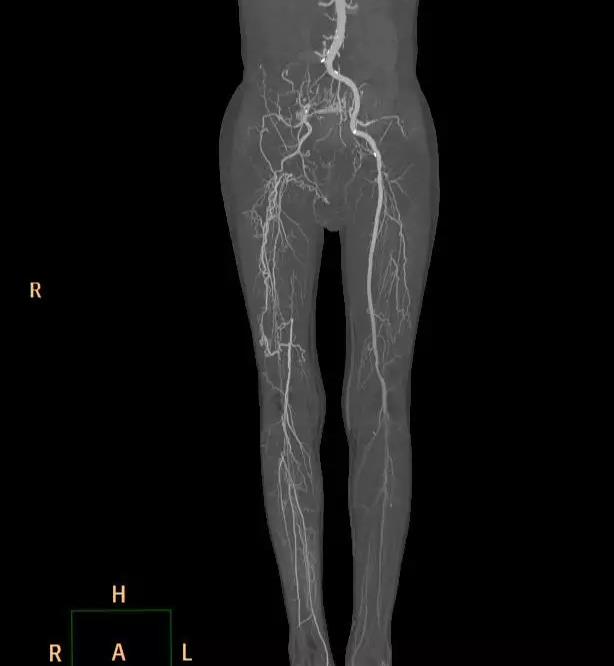

就在入院20多天前,老汉没原由突然觉得左腿疼痛,伴麻木,发凉,无力。赶紧去当地市级医院就诊,查彩超及CTA发现(图1),双侧髂动脉及双下肢动脉长段闭塞!病因是找到了,但当地医院束手无策,巧合的是老汉有一个亲戚是郑州大学五附院的护士长,听说老汉得了这个病,让他赶紧来找王兵教授。护士长告诉老汉王兵教授是河南省血管外科的首席专家,也是郑州大学五附院的副院长、郑州大学血管外科研究所所长,在治疗复杂下肢动脉硬化闭塞性病变上经验非常丰富。

图1 外院CTA

术后因患者长时间留置动脉鞘管,易导致菌血症、鞘管内血栓形成等并发症。施敏护士长带领的护理团队术后严格无菌操作,按时冲洗鞘管,避免了上述并发症的发生。5天后复查造影(图3,4,5,6,7):腹主动脉,左侧髂动脉,股动脉全程通常,膕动脉短段闭塞,但周围侧枝血管丰富,可较好的代偿至膝下。患者左下肢的皮肤温度和颜色明显改善,下肢疼痛,发凉等缺血症状缓解,出院前复查CTA效果良好(图8)。

图8 术后复查CTA